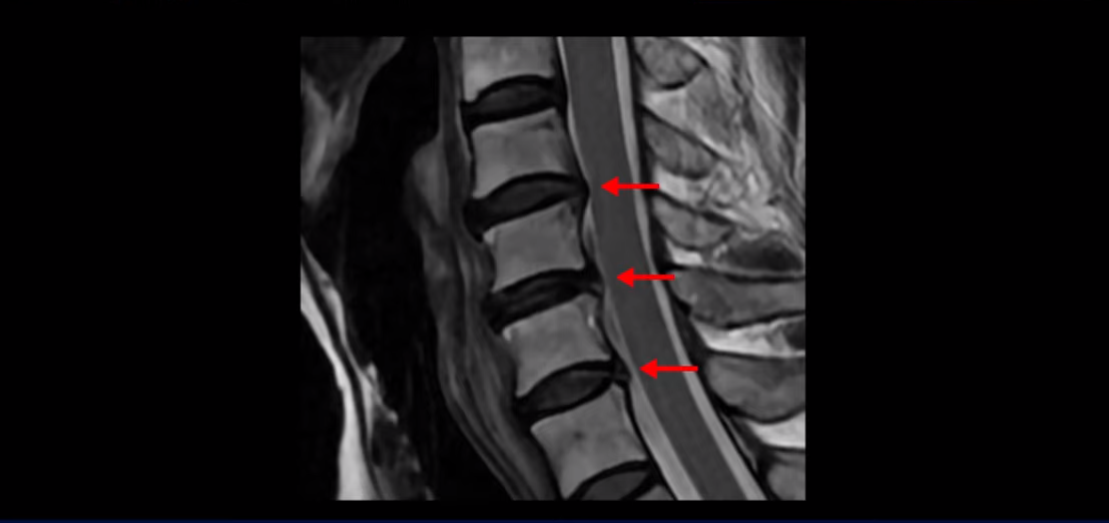

이분 MRI를 보면 세 마디의 퇴행성 목디스크가 있습니다. 4번 5번, 5번 6번과 6번 7번이 세 마디인데

디스크 파열은 4번 5번이 제일 심합니다.

중앙 오른쪽으로 수핵이 밀려 나와있고 밑으로 흘러 내려가 있습니다.

그런데 이 환자분의 방사통은 왼쪽 어깨와 팔입니다. 그래서 이 4번 5번 디스크 파열은 왼쪽 방사통의 원인이 아닌 걸로 보입니다. 6번 7번을 보면 디스크가 왼쪽으로 밀려 나와 있고, 뼈도 자라나 있습니다.

이렇게 뼈가 자라나 있으니까, 신경가지가 빠져나가는 추간공을 보면 여러 마디가 다 좁아져 있습니다.

이런 걸 협착이라고 합니다. 목이 협착이 진행된 것이죠. 그런데 왜 목디스크, 목 협착 치료가 허리보다 훨씬 더 쉽고 빠르다고 하는 걸까요? 그 이유는 목은 하중을 허리보다 훨씬 더 적게 받기 때문입니다. 하중을 적게 받으니까 신경 눌림이 조금만 줄어도 증상이 훨씬 더 빠르게 좋아지는 것입니다.